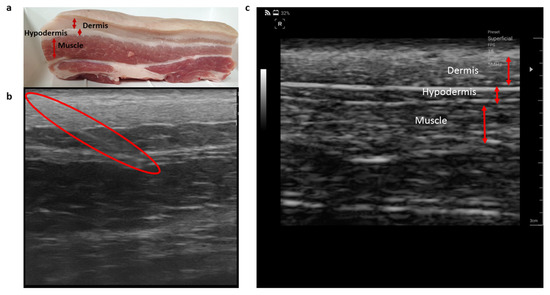

The segmental layers of pork tissue used for the experiment, including the dermis, hypodermis, and muscle is shown in Figure 3. From the ultrasound image of the pork tissue, the structure and thickness of the tissue layers in the pork meat could be found. With the aid of ultrasonography, the tip of the monopolar injection needle was successfully inserted and positioned in the specific tissue layer. The electrical impedance data of the tissue layers were measured while the needle position was observed in real-time by ultrasonography.

Figure 3. (a) Pork tissue used for the experiment, (b) ultrasound image of the pork tissue showing the needle location in muscle layer indicated by the red colored boundary, and (c) the different thickness of the tissue layers indicated by the red arrows.